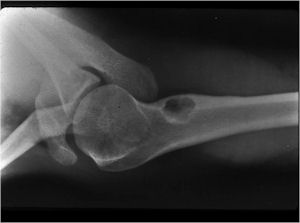

Plain X-rays:

- Geographic, circumscribed lesion usually around 5cm in size.

- There may be expansion of bone, cortical thinning and cortical breakthrough. A soft tissue mass may accompany this lesion but the soft tissue component is usually contained by the periosteum.

- The periosteum remains intact around the soft tissue component. Might need a CT scan to detect the subtle calcification (Egg Shell Rim of Calcification) associated with an intact periosteal reaction

- The lesion may be entirely radiolucent but usually shows some degree of mineralization. Mineralization may appear stippled like cartilage but do not see chondroid pathologically. Mineralization is sometimes better detected on a CT scan rather than an x-ray.